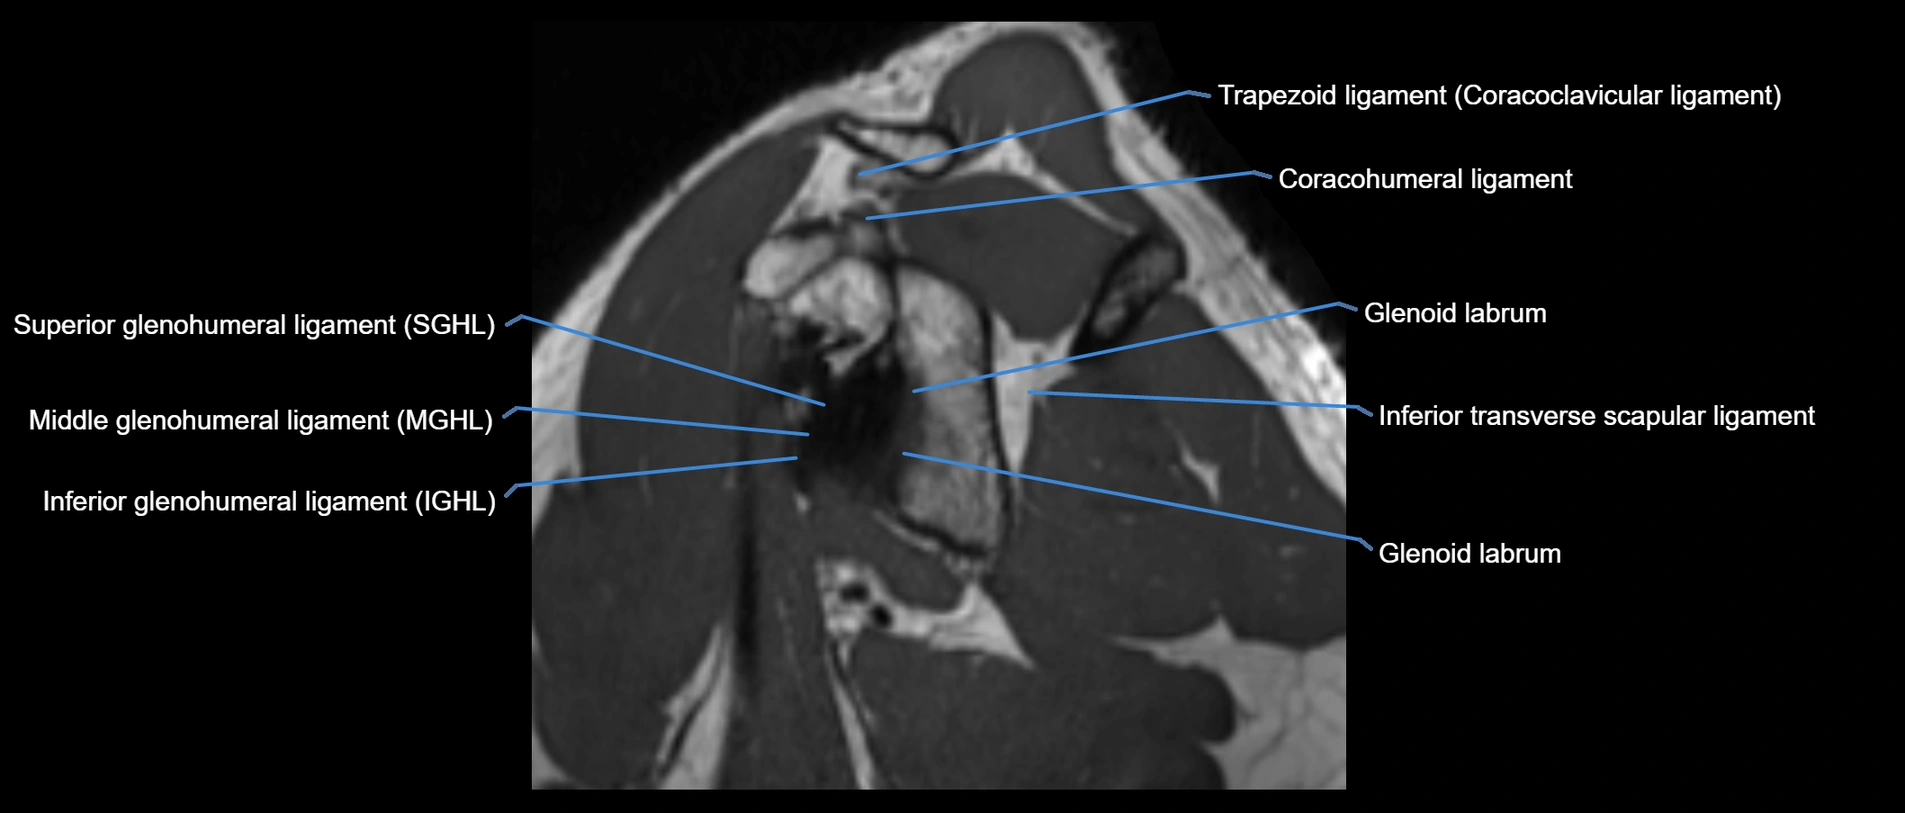

MRI images

image